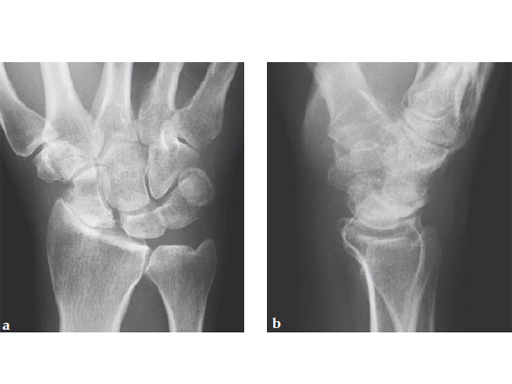

Case 2: Early degenerative wrist stage 3 secondary to a necrotic and collapsed proximal pole nonunion.

Case provided by Ariane Scheller, Berlin, Germany

Fig 1ab Preoperative x-rays. Note the carpal collapse a a b nd DISI deformity.